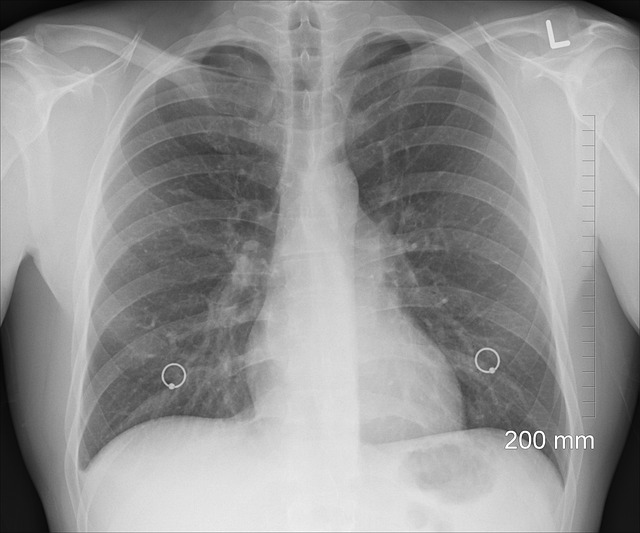

건강을 다루는 이야기에서 가장 무서운 단어가 바로 무증상이죠? 실제로 흔한 증상 중 하나인 무증상은 폐암의 대표적인 증상입니다. 폐암은 초기 증상이 나타나지 않는 암으로 알려져 있어 증상이 발현된 이후는 보통 4기나 말기 판정을 받는 경우가 대부분입니다. 초기에는 감기처럼 가벼운 기침으로 넘기는 경우도 많으며, 통증이 나타났다가 없어졌다가 반복되기도 합니다. 폐암의 좋은 예방법은 매년 건강검진을 통한 흉부 엑스레이나 지속적인 검사가 가장 좋은 예방법입니다.